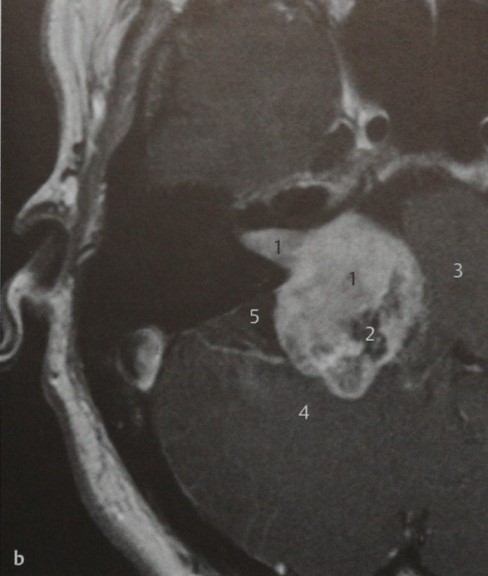

Пациент, обратившийся по поводу подостро развившейся односторонней тугоухости. МРТ:Т1-взвешенное изображение в горизонтальной проекции после введения препарата гадолиния. На данной МРТ представлен случай более крупной шванномы преддверно-улиткового нерва. Опухоль накапливает КС, заполняет внутренний слуховой проход, и значительная часть ее достигает мостомозжечкового угла (1). Учитывая отчетливое контрастное усиление и характерную локализацию опухоли, можно предположить с большой долей вероятности, что это шваннома преддверно-улиткового нерва. Участки опухоли, которые не накапливают КС (2), по-видимому, соответствуют кистозному перерождению, часто наблюдаемому при шванномах. Видно, что опухоль сдавливает ствол мозга (3) и мозжечок (4). Отмечается слабо выраженная реакция твердой мозговой оболочки, которая более характерна для менингиомы. Кзади от опухоли, возможно, имеется арахноидальная киста (5), которая иногда образуется из-за скопления ЦСЖ, связанного с вызываемым опухолью масс-эффектом.